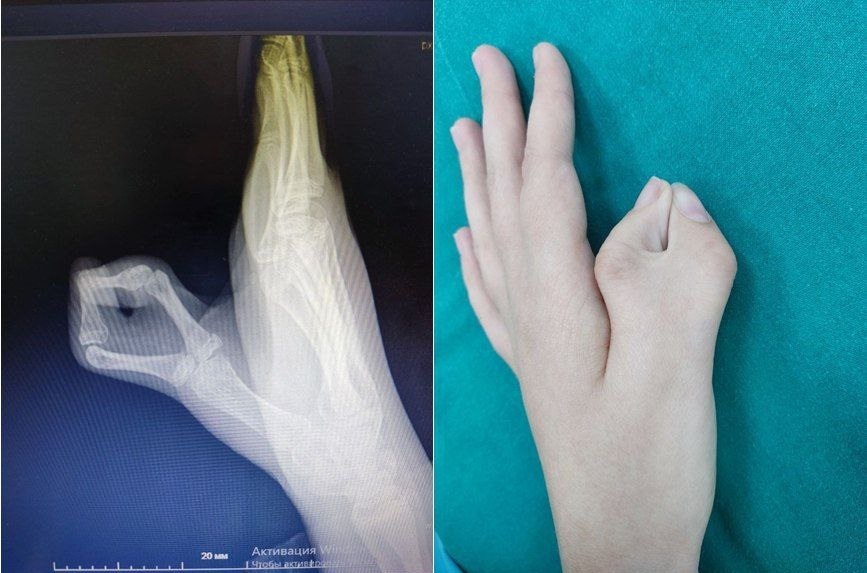

Тюменские медики успешно прооперировали девочку с редкой аномалией. Пациентом ОКБ № 2 стала 12-летняя девочка с дополнительным большим пальцем на кисти, сообщает инфоцентр правительства региона.

Хирургическое вмешательство выполнил травматолог-ортопед, кистевой хирург детского стационара Игорь Супрунов. В ходе операции медики удалили добавочный палец, стабилизировали пястно-фаланговый сустав, скорректировали ось фаланги, перенесли точку фиксации длинного сгибателя.

Восстановление пациентки проходит успешно. Через две недели после операции девочке сняли швы, а через полтора месяца рентгеновский контроль показал полное срастание фаланги. Впереди – удаление спиц и курс реабилитации.